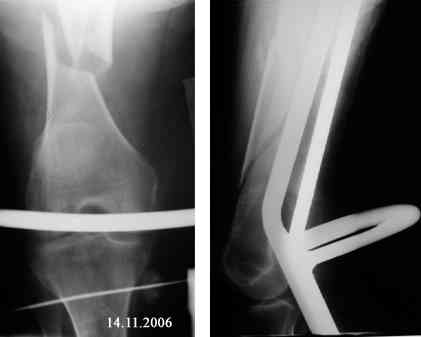

В продолжение темы оскольчатого перелома бедренной кости.

Р-граммы в динамике